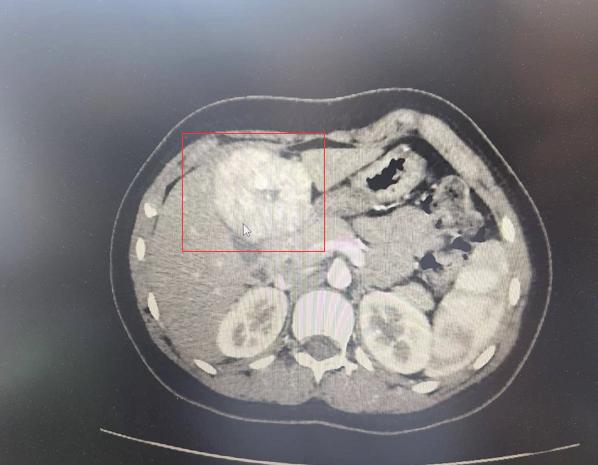

11岁的美美,2022年9月由副院长高志刚主刀,在浙大儿院成功开展达芬奇机器人肝脏肿瘤切除手术。术后一年,恢复良好。回访中,妈妈表示:“手术效果很好,现在她跟其他同龄孩子没有区别,一直在正常上学。当时很担心肿瘤切除不干净,现在来看达芬奇手术确实有优势,孩子术后恢复良好,同时留下的疤痕也非常小。”